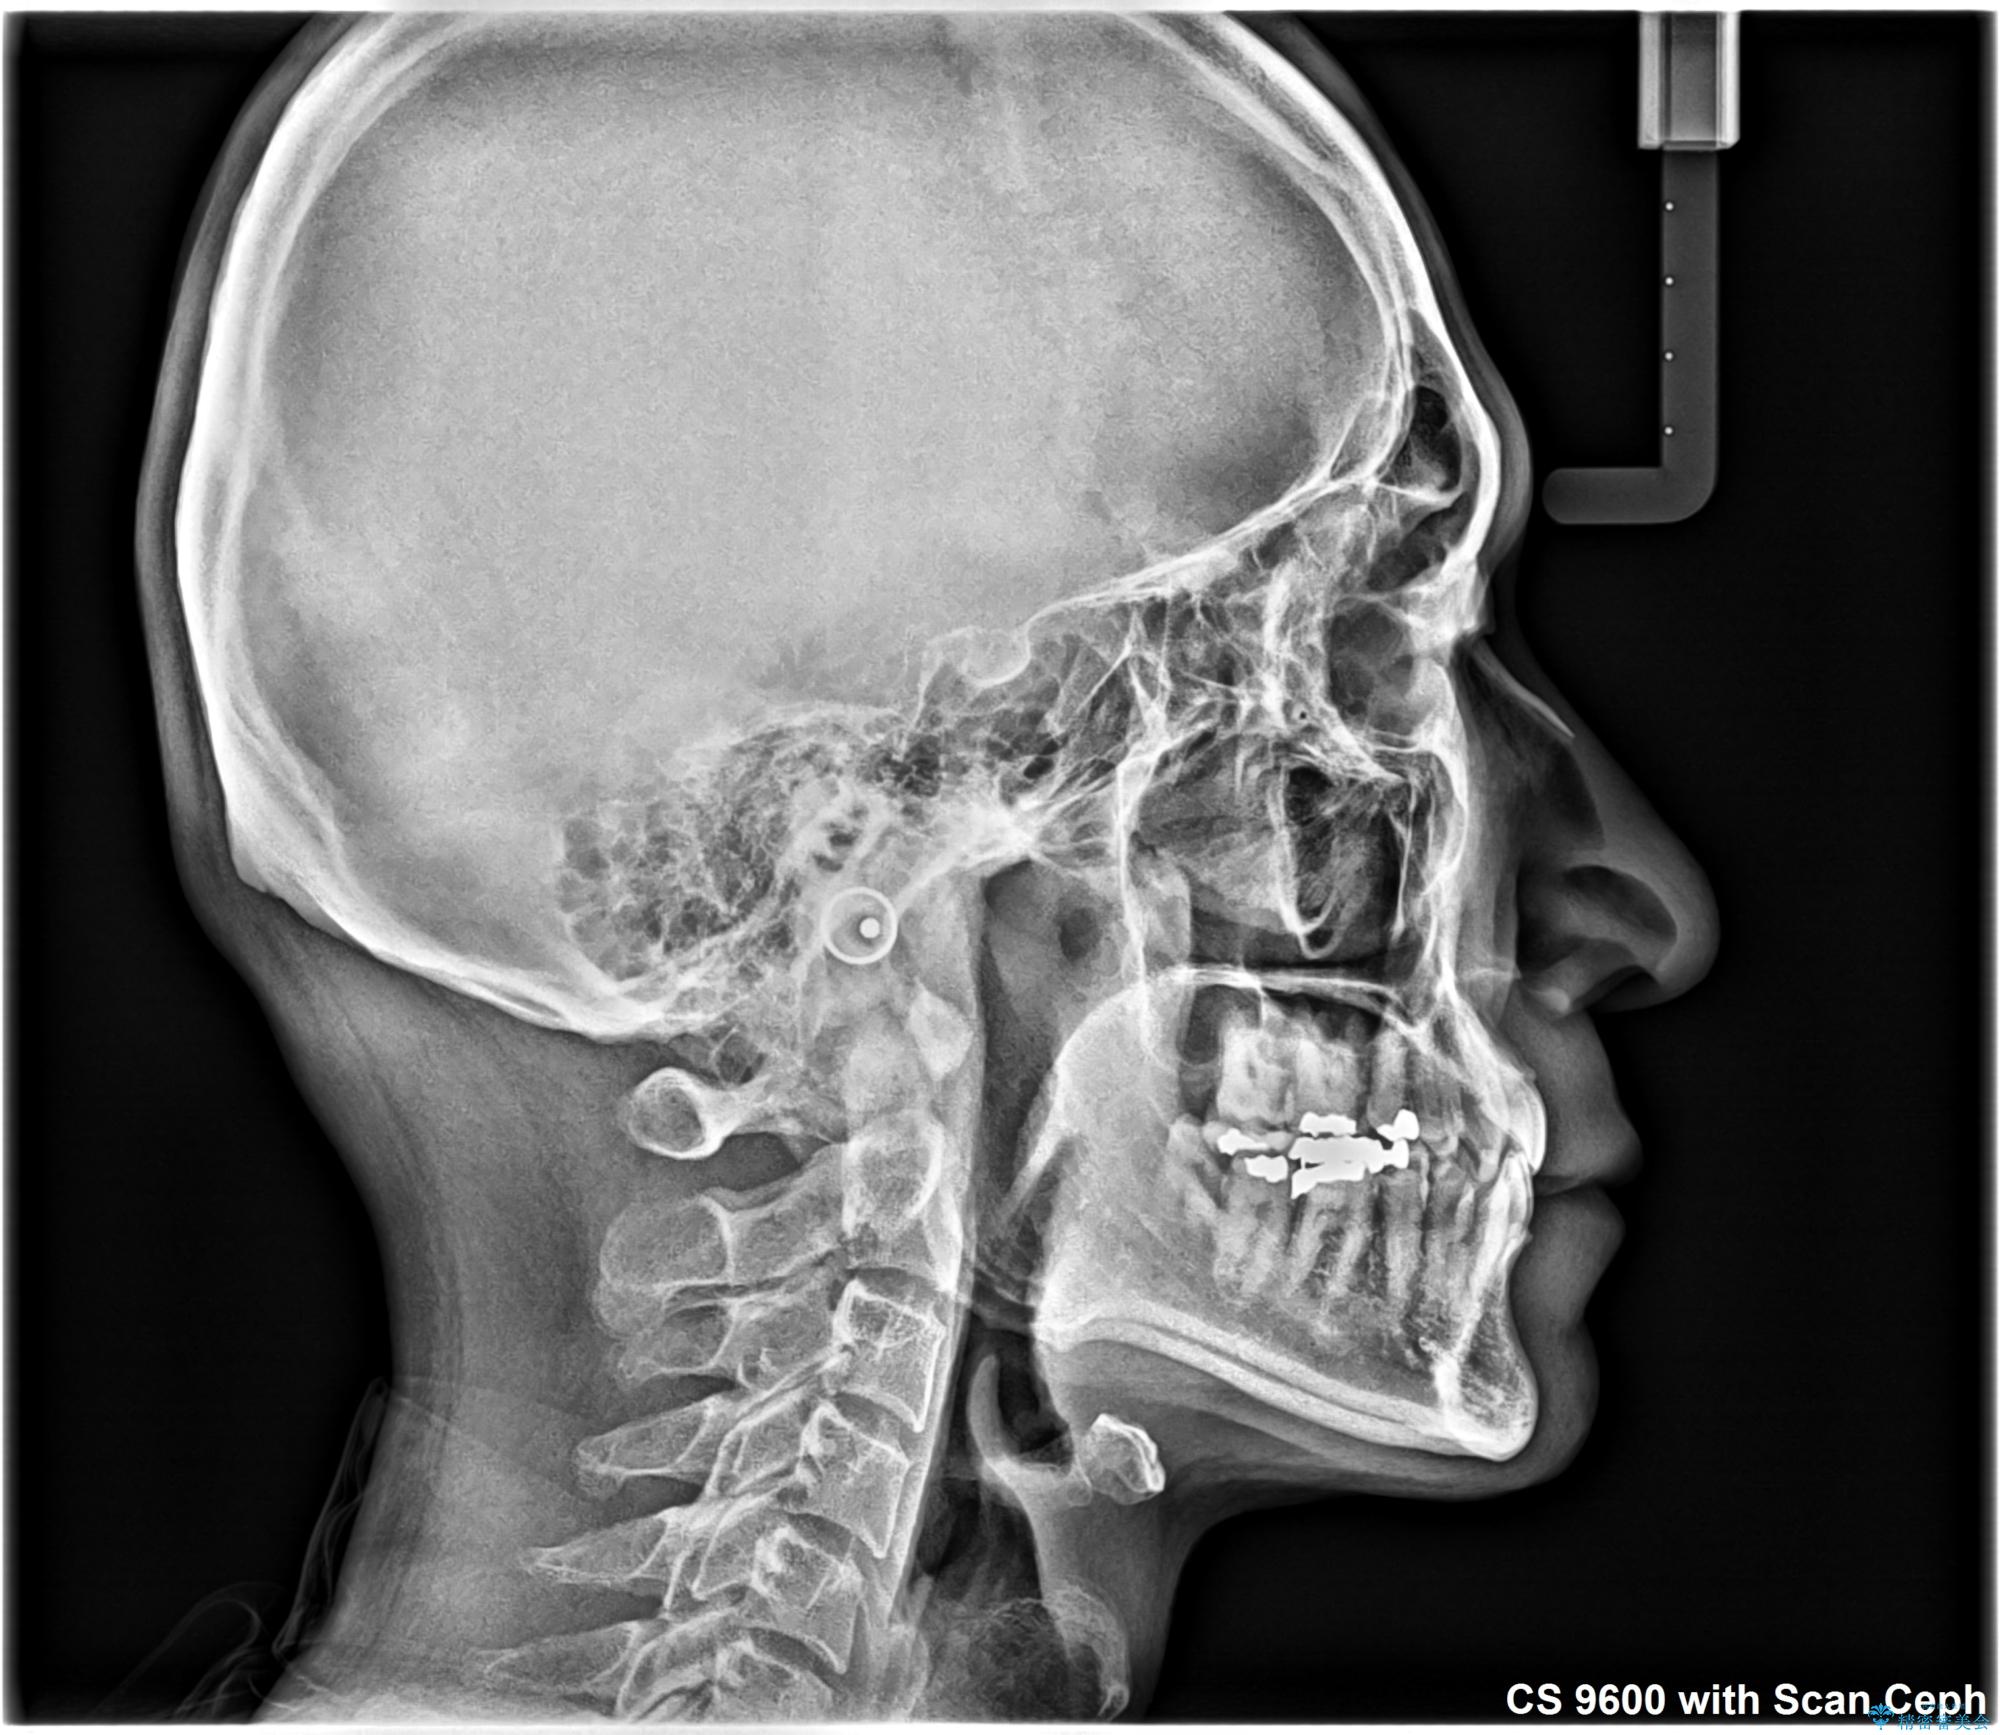

- 前歯のデコボコと隙間の空いた歯列を気にして来院された患者様です。

下顎前歯が隠れるほどのディープバイトにより、強い咬合力と突き上げで上顎歯列に隙間が空いている状態でした。

手前に傾斜している奥歯をワイヤー装置で立ち上がらせ、咬み合わせの高さを挙上することで突き上げを解消し、空隙歯列を改善していくこととしました。